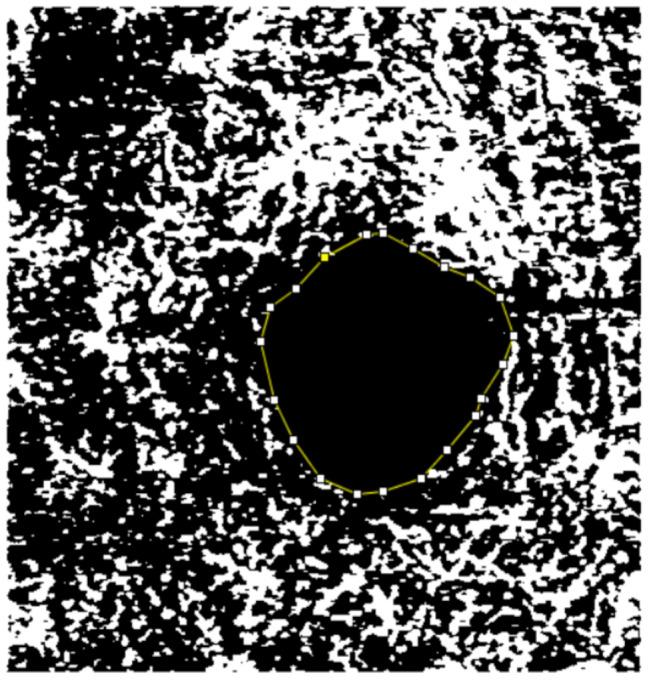

The objective of this study was to establish a comparison between the vessel density (VD) and foveal avascular zone (FAZ) of patients with type 2 diabetes mellitus (T2DM) who lacked clinical signs of diabetic retinopathy (DR) and non-diabetic patients using optical coherence tomography angiography (OCTA).

A cross-sectional comparative case-control study (unpaired) was carried out at two tertiary hospitals. All subjects underwent optical coherence tomography angiography (OCTA) examination (DRI OCT Triton Swept Source, Topcon, Japan). The average VD in the superficial capillary plexus (SCP) and the deep capillary plexus (DCP), the FAZ area (mm2) in SCP, and DCP were taken into analysis. The time since the diagnosis of T2DM was used to stratify patients with diabetes between 5 and 10 years and those with a diagnosis of more than 10 years.

Compared to non-diabetic controls, the parafoveal VD in both SCP and DCP was significantly reduced in the eyes of T2DM patients without clinical DR (p < 0.001). Additionally, the VD was also statistically reduced in T2DM diagnosed more than 10 years ago compared to T2DM cases diagnosed between 5 and 10 years ago (p < 0.001). The FAZ area in both plexuses was larger in T2DM eyes compared to controls (p < 0.001). The FAZ area was enlarged in DCP (p = 0.04), but there was no significance of FAZ area in SCP when comparing patients with T2DM diagnosed between 5 and 10 years ago to those diagnosed more than 10 years ago (p = 0.06).

In diabetic patients with long-term diagnosed disease, OCTA was shown to be capable of detecting preclinical microvascular foveal abnormalities prior to the development of clinically apparent retinopathy. According to our findings, OCTA has the potential to be a promising instrument for the early detection of vascular micro-abnormalities and the routine screening of diabetic eyes.